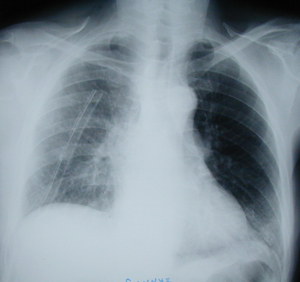

Figure 4

Postero-anterior postoperative chest X-ray, three days after right upper lobectomy. Complete expansion of the remaining lung. Also chest – tube is visible in the right hemithorax.